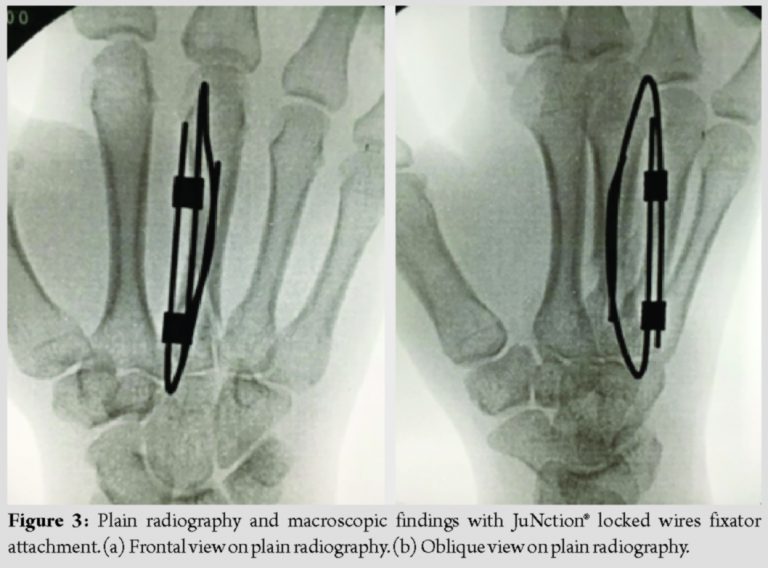

Surgery was performed under brachial plexus block 6 days after injury. A 1.2-mm mini fixator pin was percutaneously inserted antegradely from the base of the metacarpal bone as an intramedullary pinning and another 1.2-mm mini fixator pin was retrogradely inserted from a site proximal to the Metacarpophalangeal (MP) joint capsule of the metacarpal bone neck as intramedullary pinning (Fig. 2a and b). These pins were inserted through bone holes of cortex made of the same size pins. In addition, the inserted two mini fixator pins were connected using “JuNction” while retaining the manually reduced position to externally reduce and fix the fracture region (Fig. 3a and b). In this technique, the skin incision was not necessary because the pins were inserted percutaneously. The selection of wire diameter was dependent on the diameter of the medullary cavity of the metacarpal bone since two pins should be placed intramedullary. The c-arm is essential because intramedullary pinning was done by fluoroscopy. The operation time in this case was 30 min.

Various surgical methods for metacarpal shaft fractures have been reported [4,5]. Simple wire fixation, soft wire fixation, and intramedullary pinning require post-operative immobilization because the fixation force is insufficient and early initiation of range of motion training after surgery is difficult [6]. In contrast, strong fixation can be acquired by open surgery using a locking plate and range of motion training can be initiated early after surgery, but it has a risk for several complications. Reported complications of plate fixation include keloid scar formation of the wound region, adhesion of the extensor tendon, and joint contracture [7]. Screw fixation is a surgical procedure acquiring favorable fixation through a small skin incision, but it is not indicated for short oblique and transverse fractures into which a screw cannot be inserted. Moreover, Bouquet technique is a great way to get early mobility, but it still takes weeks of “buddy taping” to prevent malrotation [8]. The locked wires fixator we used is also suitable for the prevention of post-operative malrotation and basically there is no need for any taping. In general, the external fixator is used for open or comminuted fractures, severe soft-tissue damage, and comminuted intra-articular fractures. External fixation, which used to be bulky in the past, has been refined and expanded in recent years [9]. The locked wires fixator used in this case is a device capable of freely connecting pins which can be used more easily as compared with the conventional external fixator. The device is expected to expand its indication for fractures due to this simplicity. A biomechanical study on the fixing force of intramedullary rods suggested that rotational stability is improved by the insertion of several intramedullary rods [2]. It is also well-known that fixation is favorable as the rate of medullary cavity occupation by intramedullary rods increases [10]. In the present patient, the width of the narrowest region of the 3rd metacarpal bone was 2.5 mm on plain radiography. The medullary cavity occupation rate was to be 96% when two 1.2-mm mini fixator pins were inserted. There are 1.2, 1.5, and 1.8 mm mini fixator pins in JuNction® locked wire fixator adopted in this case and the device is applicable to a maximum of 3.6 mm medullary cavity in this surgical procedure, in which several wires were not inserted from a site proximal to the metacarpal bone, unlike Foucher’s modification, but two mini fixator pins were inserted from proximal and distal sites, respectively, as intramedullary pinning. This is a new breakthrough procedure facilitating: (1) Acquisition of a sufficient medullary cavity occupation rate for which favorable fixation of the fracture region can be expected and (2) prevention of postoperative malrotation through 1.2 mm × 2 = 2.4 mm rod formation externally by the two mini fixator pins. Furthermore, this surgical procedure may be selected as an esthetically useful method making a small wound because it can be percutaneously applied. Miyamoto et al. recommended the use of an external fixator, Meta-HUS®, which connects wires for fixation in treatment of 5thcarpometacarpaljoint dislocation fractures [3], because bone fragments can be strongly held compared with that in previous wire fixation and wires are inserted at the MP joint flexion position to permit finger movement early after surgery, expecting prevention of MP joint contracture. Furthermore, this external fixator is capable of freely connecting the wires, for which expansion of the indication for treatment of finger fractures may be expected. There are several limitations to this technique. First, the shortening of the metacarpal bone was not controlled. On the final follow-up (12 months after surgery), bone fusion had been acquired with the shortening of the third metacarpal bone (Fig. 4a). However, the limitation of the range of motion of the finger joints including the MP joint was not observed (Fig. 4c-e). It is considered that although the shortening of the metacarpal bone remained because the early movement was possible under the good fixing force of the locked wires fixator, the limitation of the range of motion did not occur. Furthermore, as with general percutaneous pinning, it is necessary to recognize the pin tract infection and the risk of the extensor tendon and superficial nerve injury or irritation.